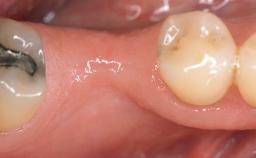

A 30-year-old woman was referred by her general dentist for evaluation of an esthetic complication related to previous implant treatment for congenitally missing maxillary lateral incisors. The patient’s chief complaint was the inadequate esthetic appearance of her smile. The case demonstrates the use of a combined approach to achieve optimal results. Two different flap designs - a tunnel technique and a coronally advanced flap - are employed based on the surgical objectives for the affected site.

Soft Tissue Grafting Yes